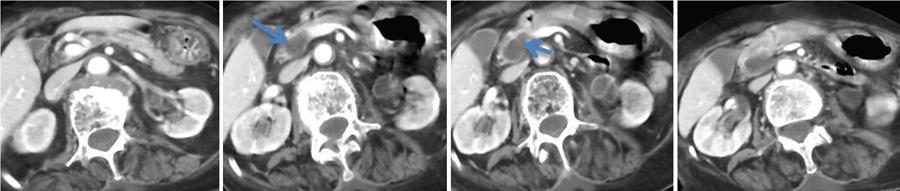

Ritu K. Kashikar, Shrinivas B. Desai, Pooja Punjani Vyas, Nilesh Doctor, Vivek Shetty Advancement and extensive use of imaging in recent times has to lead to increased detection and recognition of cystic pancreatic masses. Imaging however, plays a vital role in noninvasive diagnosis of these lesions, avoiding unnecessary intervention and planning management and follow up guidelines. The aetiology of pancreatic cysts ranges from primary cystic neoplasm to cystic degeneration of solid neoplasm to nonneoplastic cysts (Table 9.19.1). Cystic tumours of the pancreas comprise around 10%–15% of cystic lesions of the pancreas. The aim of this chapter is to educate the reader regarding imaging features of cystic lesions of pancreas, how to differentiate between cysts which can be left alone and those that require further management and also emphasize on latest international guidelines used in stratification of these lesions. Cystic pancreatic lesions are often incidentally detected on USG abdomen performed for other reasons. Although USG is an excellent modality for evaluation of cystic lesions elsewhere, it is unable to adequately characterize pancreatic cysts due to retroperitoneal location of the organ and other confounding factors such as obesity and gases. Most lesions detected on USG require characterization with either MDCT or MRI with MRCP. CEUS improves accuracy in the differentiation between a solid and a cystic lesion and also in determining whether enhancing septa or nodules are present within the cystic lesion. Currently USG also does not have a role in follow up algorithms of pancreatic cystic lesions. Multidetector CT evaluation of pancreatic lesions is best performed with a multiphasic technique (Table 9.19.2). The phases include a precontrast scan, an early arterial angiographic phase, a pancreatic parenchymal phase, and a portal venous phase. The precontrast scan is important for detection of calcification, which may be diagnostic of some lesions. Mucinous cystic neoplasms may be hyperdense on nonenhanced scan suggesting mucin content or haemorrhage. The arterial phase aids in detection of hyperenhancement neovascularity and arterial involvement in pancreatic masses. Optimal parenchymal enhancement of the pancreas is achieved at 35–45 seconds after initiation of injection of contrast agent. This is the pancreatic parenchymal phase. It is in this phase that the tumour pancreas contrast is maximum (Fig. 9.19.1, Table 9.19.3). Most hypoenhancing pancreatic lesions are best detected in this phase. The portal venous phase allows in detection of venous involvement and hepatic metastasis. Delayed phase is typically not required in cystic masses. MDCT has an accuracy of 56%–85% for characterization of cystic pancreatic lesions. MR imaging affords the best noninvasive means for the evaluation of cystic lesions of the pancreas due to superior soft tissue resolution. The helpful distinguishing characteristics of cystic pancreatic lesions, morphology of septae, relation to pancreatic duct are easier to detect at MR imaging and MR cholangiopancreatography (MRCP) than at CT (Table 9.19.4). Studies however indicate that MDCT and MRI are comparable in identifying malignant behaviour of cystic pancreatic lesions. The MRI protocol for evaluation of cystic lesions of pancreas includes T2-weighted single-shot fast spin-echo, T1-weighted in-phase and opposed-phase gradient echo, diffusion-weighted imaging, T2-weighted fat-suppressed fast spin-echo. Three-dimensional T1-weighted fat-suppressed spoiled gradient-echo T2-weighted MRCP. Postcontrast protocol includes dynamic three-dimensional T1-weighted fat-suppressed spoiled gradient-echo (in arterial, pancreatic and portal venous phases) (Fig. 9.19.2, Table 9.19.3). DWI has not found much utility in cystic neoplasms owing to overlap in ADC values. Some studies suggest role in distinguishing malignant from benign tumours in the case of mucinous cystadenoma and IPMN. Secretin is a peptide hormone produced in the intestinal mucosa, which stimulates the secretion of bicarbonate-rich fluid into the pancreatic ducts and transiently increases the tone of the sphincter of Oddi. The increased fluid distention of the pancreatic duct allows better study of ductal anatomy and identifying communication of pancreatic cystic lesions with the pancreatic duct. EUS is excellent in characterization of cystic lesions of pancreas. The proximity between the transducer and the lesions allows precise definition of the structural component of the cysts and components such as small mural nodules are better visualized with EUS than with other modalities. The other advantage of EUS is that cysts fluid aspiration and cytology can be performed. Tumour markers, genetic markers can be evaluated in the aspirated fluid. This allows comprehensive evaluation of cystic lesion. EUS also has therapeutic advantages allowing endoscopic draining of pseudocysts. Recently endoscopic ablation of cysts has been performed. These advantages have led to increasing use of EUS in recent years. This modality is however not indicated in all lesions and imaging should be able to stratify lesions requiring further invasive investigations. Studies have found PET CT comparable to PET alone or CT to determine presence of malignancy in cystic lesions. False positive findings may however be problematic. There is however no consensus for routinely using PET CT in characterization of cystic pancreatic masses. Serum CA19-9 and CEA are routinely done in all pancreatic masses. Though role in cystic lesions is still controversial. Serous cystadenoma is a benign neoplasm composed of glycogen-rich epithelial cells that form innumerable small thin-walled cysts containing serous fluid. It is the prototype microcystic pancreatic neoplasm. They occur frequently in older women (median age, 65 years) and is also called as grandmother lesion. Approximately 40% of pancreatic serous cystadenoma arise from the pancreatic head and uncinate process and 60% arise from the pancreatic body and tail. Serous cystadenomas are usually discovered incidentally at imaging; however, those that are large may cause symptoms. Patients may present with abdominal pain, palpable mass, anorexia, fatigue/malaise, or weight loss. Rarely the patient may present with jaundice. Genetic alterations similar to those in VHL are seen in sporadic SCA and include tumour suppressor gene VHL mutations and overexpression of vascular endothelial growth factor (VEGF). Allelic loss in chromosome 3 have seen in up to 40% cases of sporadic SCA. Serous cystadenomas are variable in size. The size ranges from <0.1 to 25 cm. The tumours are grossly well demarcated from the surrounding parenchyma. The gross appearance of the lesions is variable. It could be microcystic, consisting of innumerable small cysts giving the macroscopic appearance of a sponge or honeycomb. The presence of multiple, microscopic SCN is characteristic of von Hippel–Lindau (VHL). This variety show a centrally located area of fibrotic scar. In Macrocystic/oligocystic variant, borders with the surrounding parenchyma are less defined and the cystic lesion generally does not exhibit a central scar. The Solid variant, the lack of cystic spaces on gross inspection often gives the initial impression of a neuroendocrine or solid pseudopapillary neoplasm. Serous cystadenomas show nonviscous, clear-to-yellow cyst fluid, which provides an important clue to the distinction of SN from mucinous neoplasms. In contrast to intraductal papillary mucinous neoplasm, there is no connection with main or branch pancreatic ducts. These are clinically benign pancreatic epithelial neoplasms exhibiting serous morphology, characterized by a monotonous, cuboidal epithelial cell proliferation with marked cytoplasmic clearing due to intracellular glycogen. The centrally located epithelial cell nuclei are uniformly round to ovoid and not particularly large or hyperchromatic. Abundant diastase-sensitive cytoplasmic glycogen is highlighted by a periodic acid–Schiff stain. These lesions do not show evidence of necrosis, infiltrative architecture, or lymphovascular/perineural invasion, and mitotic figures are generally not observed. A variably prominent pseudocapsule of fibrosis divides parenchyma from the neoplasm On USG the microcystic variant shows lobulated contour with multiple tiny anechoic cysts separated by septae. the central scar containing calcification can be seen if present. Extremely microcystic, honeycomb variant may resemble a solid lesion at conventional US. The macrocystic type, can be mixed type with multiple large (>20 mm) and small cysts, and the unilocular type, which is more difficult to differentiate from mucinous cystadenoma (MCA). Enhancement of the intralesional sepatations is seen on contrast-enhanced USG allowing better characterization of the lesion. The central scar can show homogenous enhancement. Honeycomb variety appears as a hypervascular lesion owing to its extremely microcystic morphology and may resemble solid masses like neuroendocrine tumours. Pancreatic serous cystadenoma can have a varied appearance on CT depending on the morphologic patterns. Serous cystadenomas are typically solitary but may be multiple in von Hippel–Lindau disease, causing an appearance of disseminated involvement (Table 9.19.5). As mentioned previously, the polycystic pattern is the most common appearance of serous cystadenoma. A pattern of a bosselated collection of cysts that usually number more than six is seen. Each cyst may range from a few millimetres to 2 cm in size (Fig. 9.19.5). The other classic CT features include a lobulated contour and presence of a central stellate scar with calcification. This scar is seen in 30% cases and when present is strongly suggestive of the diagnosis. The intralesional fibrous septae show early enhancement after contrast administration. This is a distinguishing feature, as serous cystadenoma is the only hypervascular lesion among the cystic pancreatic neoplasms. Tiny cysts mimicking a honeycomb are the hallmark of this variant and may be poorly depicted as individual cysts on CT. On unenhanced CT, the honeycomb pattern may appear as a well-marginated lesion with soft tissue or mixed attenuation, depending on the size of the cysts and the amount of fibrous tissue. Moderate to strong enhancement is seen in these lesions (Fig. 9.19.6). This appears as a unilocular cyst or it may contain fewer large (>2 cm) cysts. Imaging Features include a lobulated contour, lack of a prominent thickened peripheral wall, and location in the head of the pancreas (Fig. 9.19.7). Owing to its supreme soft tissue resolution, MRI is the modality of choice in diagnosis of serous cystadenomas. The classic MRI features of microcystic variant includes a lobulated lesion with multiple small T2 hyperintense and T1 hypointense cysts with intervening hypointense fibrous sepate. These lesions do not communicate with the pancreatic duct; hence no dilatation is usually seen. Dilatation of pancreatic duct has however been reported in larger lesions. After the administration of gadolinium, the hypervascularization of the central scar and of internal septa may be seen. The morphology of the honeycomb pattern may also be better depicted on MRI. Multiple tiny T2 hyperintense cysts with intervening hypointense septae are seen (Fig. 9.19.8). The oligocystic variant shows fewer larger T2 hyperintense and T1 hypointense cysts and can mimic mucinous cystadenoma. However, the lobulated contour, together with the absence of wall enhancement and a wall thickness less than 2 mm, suggest the correct diagnosis (Fig. 9.19.9) (Table 9.19.6). The differential diagnosis of serous cystadenoma depends on the variety and are listed in Tables 9.19.7 and 9.19.8. Lesions with classic imaging features do not require further investigation or fluid analysis. The fluid in classic cystadenomas is yellow in colour and does not show elevated amylase, mucin or tumour markers. Approximately 20%–50% cases show cytological positivity for periodic acid-Schiff and cytokeratin AE1 and 3. Hemosiderin laden macrophages also do not have high diagnostic accuracy and are seen in only about 43% cases. Current management guidelines suggest (Table 9.19.9). Resection involves distal pancreatectomy or Whipples, depending on location of the tumours and is currently reserved for truly symptomatic cases. Mucinous cystic tumours are a rare subset of cystic neoplasms, constituting approximately 2.5% of pancreatic exocrine tumours. TABLE 9.19.10 The defining and characteristic histopathologic feature of mucinous cystic neoplasms (MCNs) is the presence of ovarian-type stroma similar to that observed in biliary cystadenomas. International Association of Pancreatology recommend that all suspected MCNs be surgically resected. A significant female predilection is seen with approximately 99.7% cases seen in women. As opposed to serous cystadenomas these lesions occur in middle aged women and hence the term mother lesions is used to describe these. The approximate age of occurrence is 50 years with a range from 20–82 years. Mucinous cystic tumours are a dominant cyst that is round or oval and is encapsulated. MCNs may grow slowly over time, at an average rate of 4 mm per year. The most common locations are the pancreatic body and tail (up to 75%). Stromal elements similar to ovarian stroma are the hallmark and key feature that aids in differentiation from IPMN, whose stromal elements are ductal in origin. Tall columnar cells with intracellular mucin arranged in a single row or vertically, forming papillary or polypoidal projections, constitute the epithelial elements. Portions of benign appearing epithelium can be seen adjacent to areas of invasive carcinoma in the same tumour. These lesions show smooth contour on gross appearance with few internal sepate. Peripheral calcification, mural nodule if present suggest malignant cyst (Fig. 9.19.11, Table 9.19.11). Lesions may be asymptomatic in 25% cases. Patients my present with pain in abdomen. Mucinous cystadenoma can also present with pancreatitis. Considering most lesions are located in distal body and tail involvement of splenic vein may lead to left sided portal hypertension. Mucinous cystic tumour is a well-circumscribed cystic mass in the pancreas. Lesions can have an irregular contour to the wall, septations, mural nodularity, and peripheral calcifications. The lesion may however be echogenic due to high by mucin content or haemorrhage which may impair the detection of other features. CEUS may improve detection rate of septa and mural nodules. Lesions are typically well-circumscribed with smooth contour. On unenhanced CT, mucinous cystadenoma may appear hypodense or slightly hyperdense content, due to the presence of variable amount of mucin and haemorrhage. Curvilinear calcifications occur along the periphery of the lesion and are seen in 15% of cases, in contrast study enhancement of the fibrous cyst wall along with enhancement of any septations or mural nodules is seen (Figs. 9.19.12 and 9.19.13).